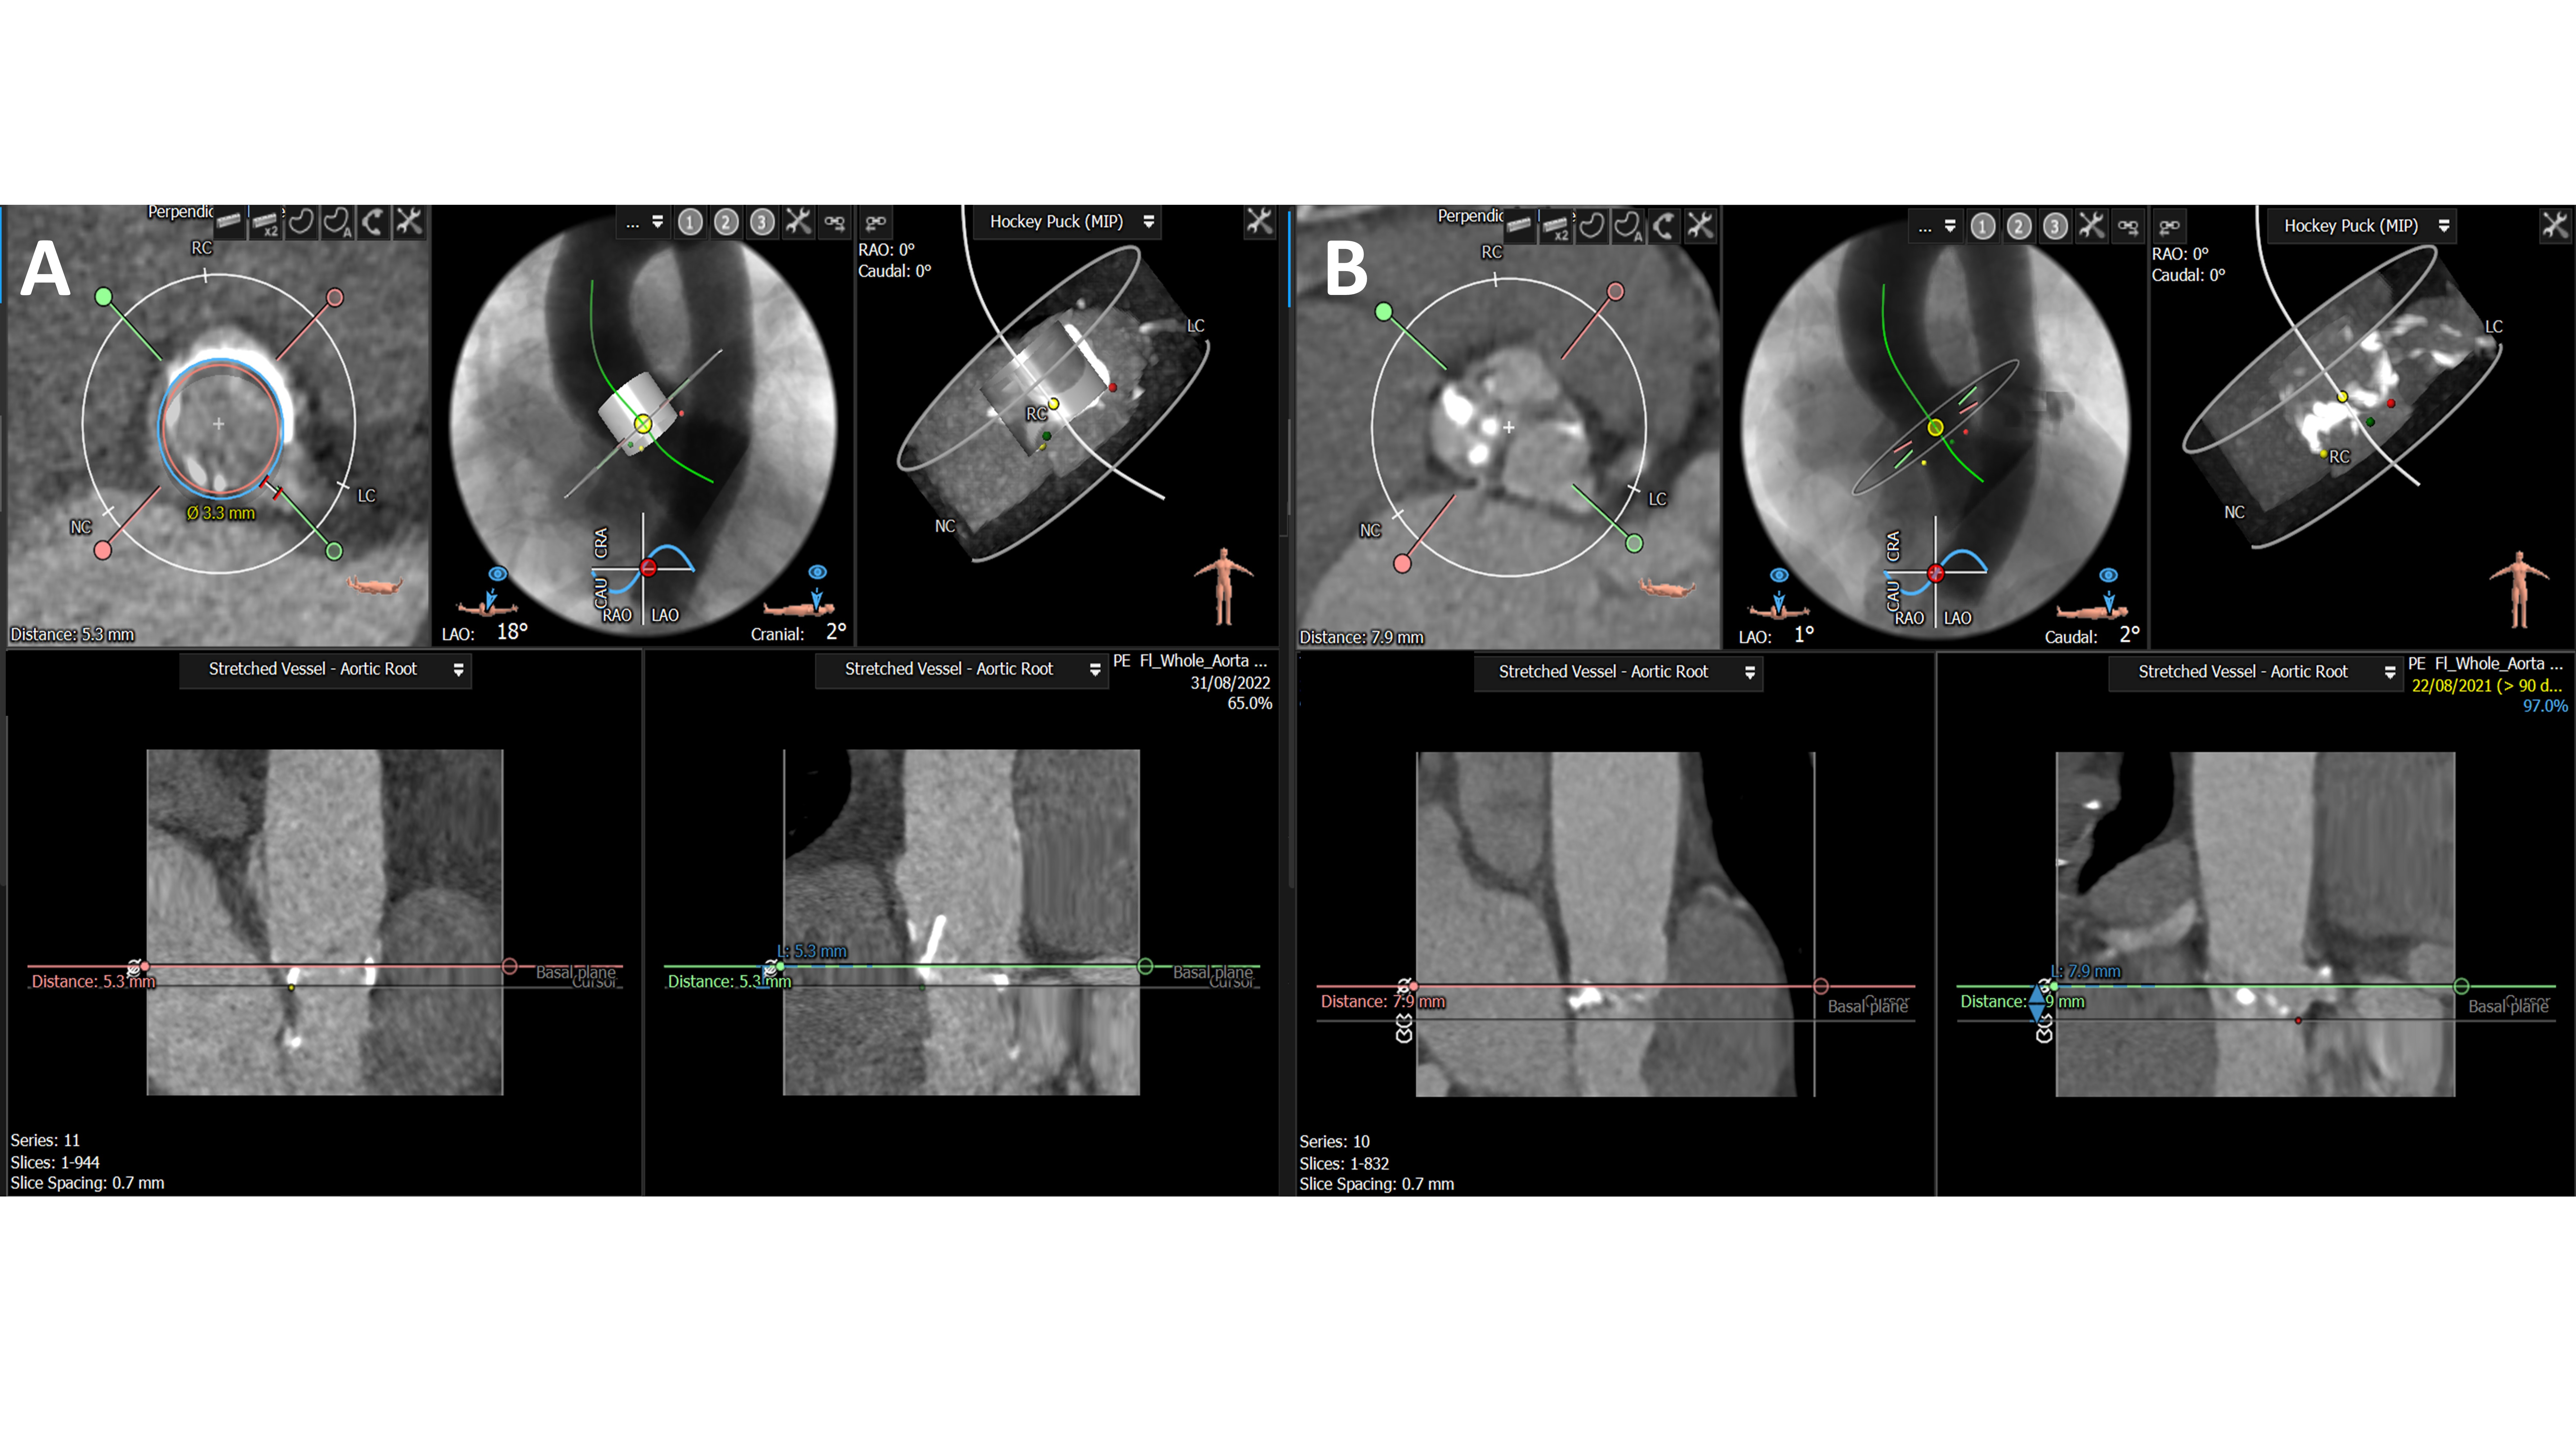

The last criterion was met in one patient only with bicuspid aortic valve stenosis. A previous TAVI attempt was abandoned as concomitant aortogram during aortic balloon valvuloplasty demonstrated evidence of CAO. Two examples of computed tomography (CT) features related to patients undergoing SKB are presented in Figure 1.

Panel B illustrates CT findings of a 72-year-old woman who underwent TAVI in a 23 mm degenerative Trifecta bioprosthetic valve (Abbott Vascular). Her left coronary height was measured at 5.3 mm with a valve-to-coronary distance of 3.3 mm.

SKB inflation was performed by introducing a noncompliant coronary angioplasty balloon to the left coronary artery over a standard angioplasty wire (Figure 2). All cases were done via a standard 6F left coronary artery guide catheter. The sizing of the balloon was angiographically determined (1:1 to the left main, LM) following selective left coronary angiography. The coronary balloon was placed between the left coronary artery and the THV. The distal “nose” of the balloon was positioned at the ostium of the LM, and its main body remained “hanging” in the aorta (Figure 1). Importantly, the position of the coronary balloon was meticulously checked to minimize any endothelial injury to the left coronary system during inflation. A SKB inflation of the SAPIEN 3 and coronary balloon (inflated up to 12 atm pressure) was performed under rapid pacing via the left ventricular wire. The coronary protection balloon was deflated immediately after deflation of the THV balloon. Subsequently, the left coronary system was checked by angiography to rule out any complications.

The features on CT suggested high risk for CAO with a median left coronary height of 7.1 (6.0-8.4) mm and SoV diameter of 24.6 (22.8-29.2) mm. Patients with previous surgical aortic valve replacement had a median VTC distance of 3.3 (2.9-3.6) mm. The median right coronary height was 14.0 (12.5-16.3) mm. Individual patients’ CT characteristics are presented in Table 2.